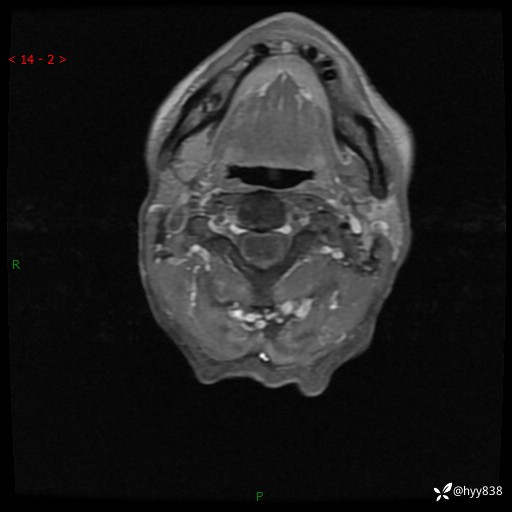

颈椎MRI平扫(sag T1WI+T2WI-fs+axi T2WI)

CE